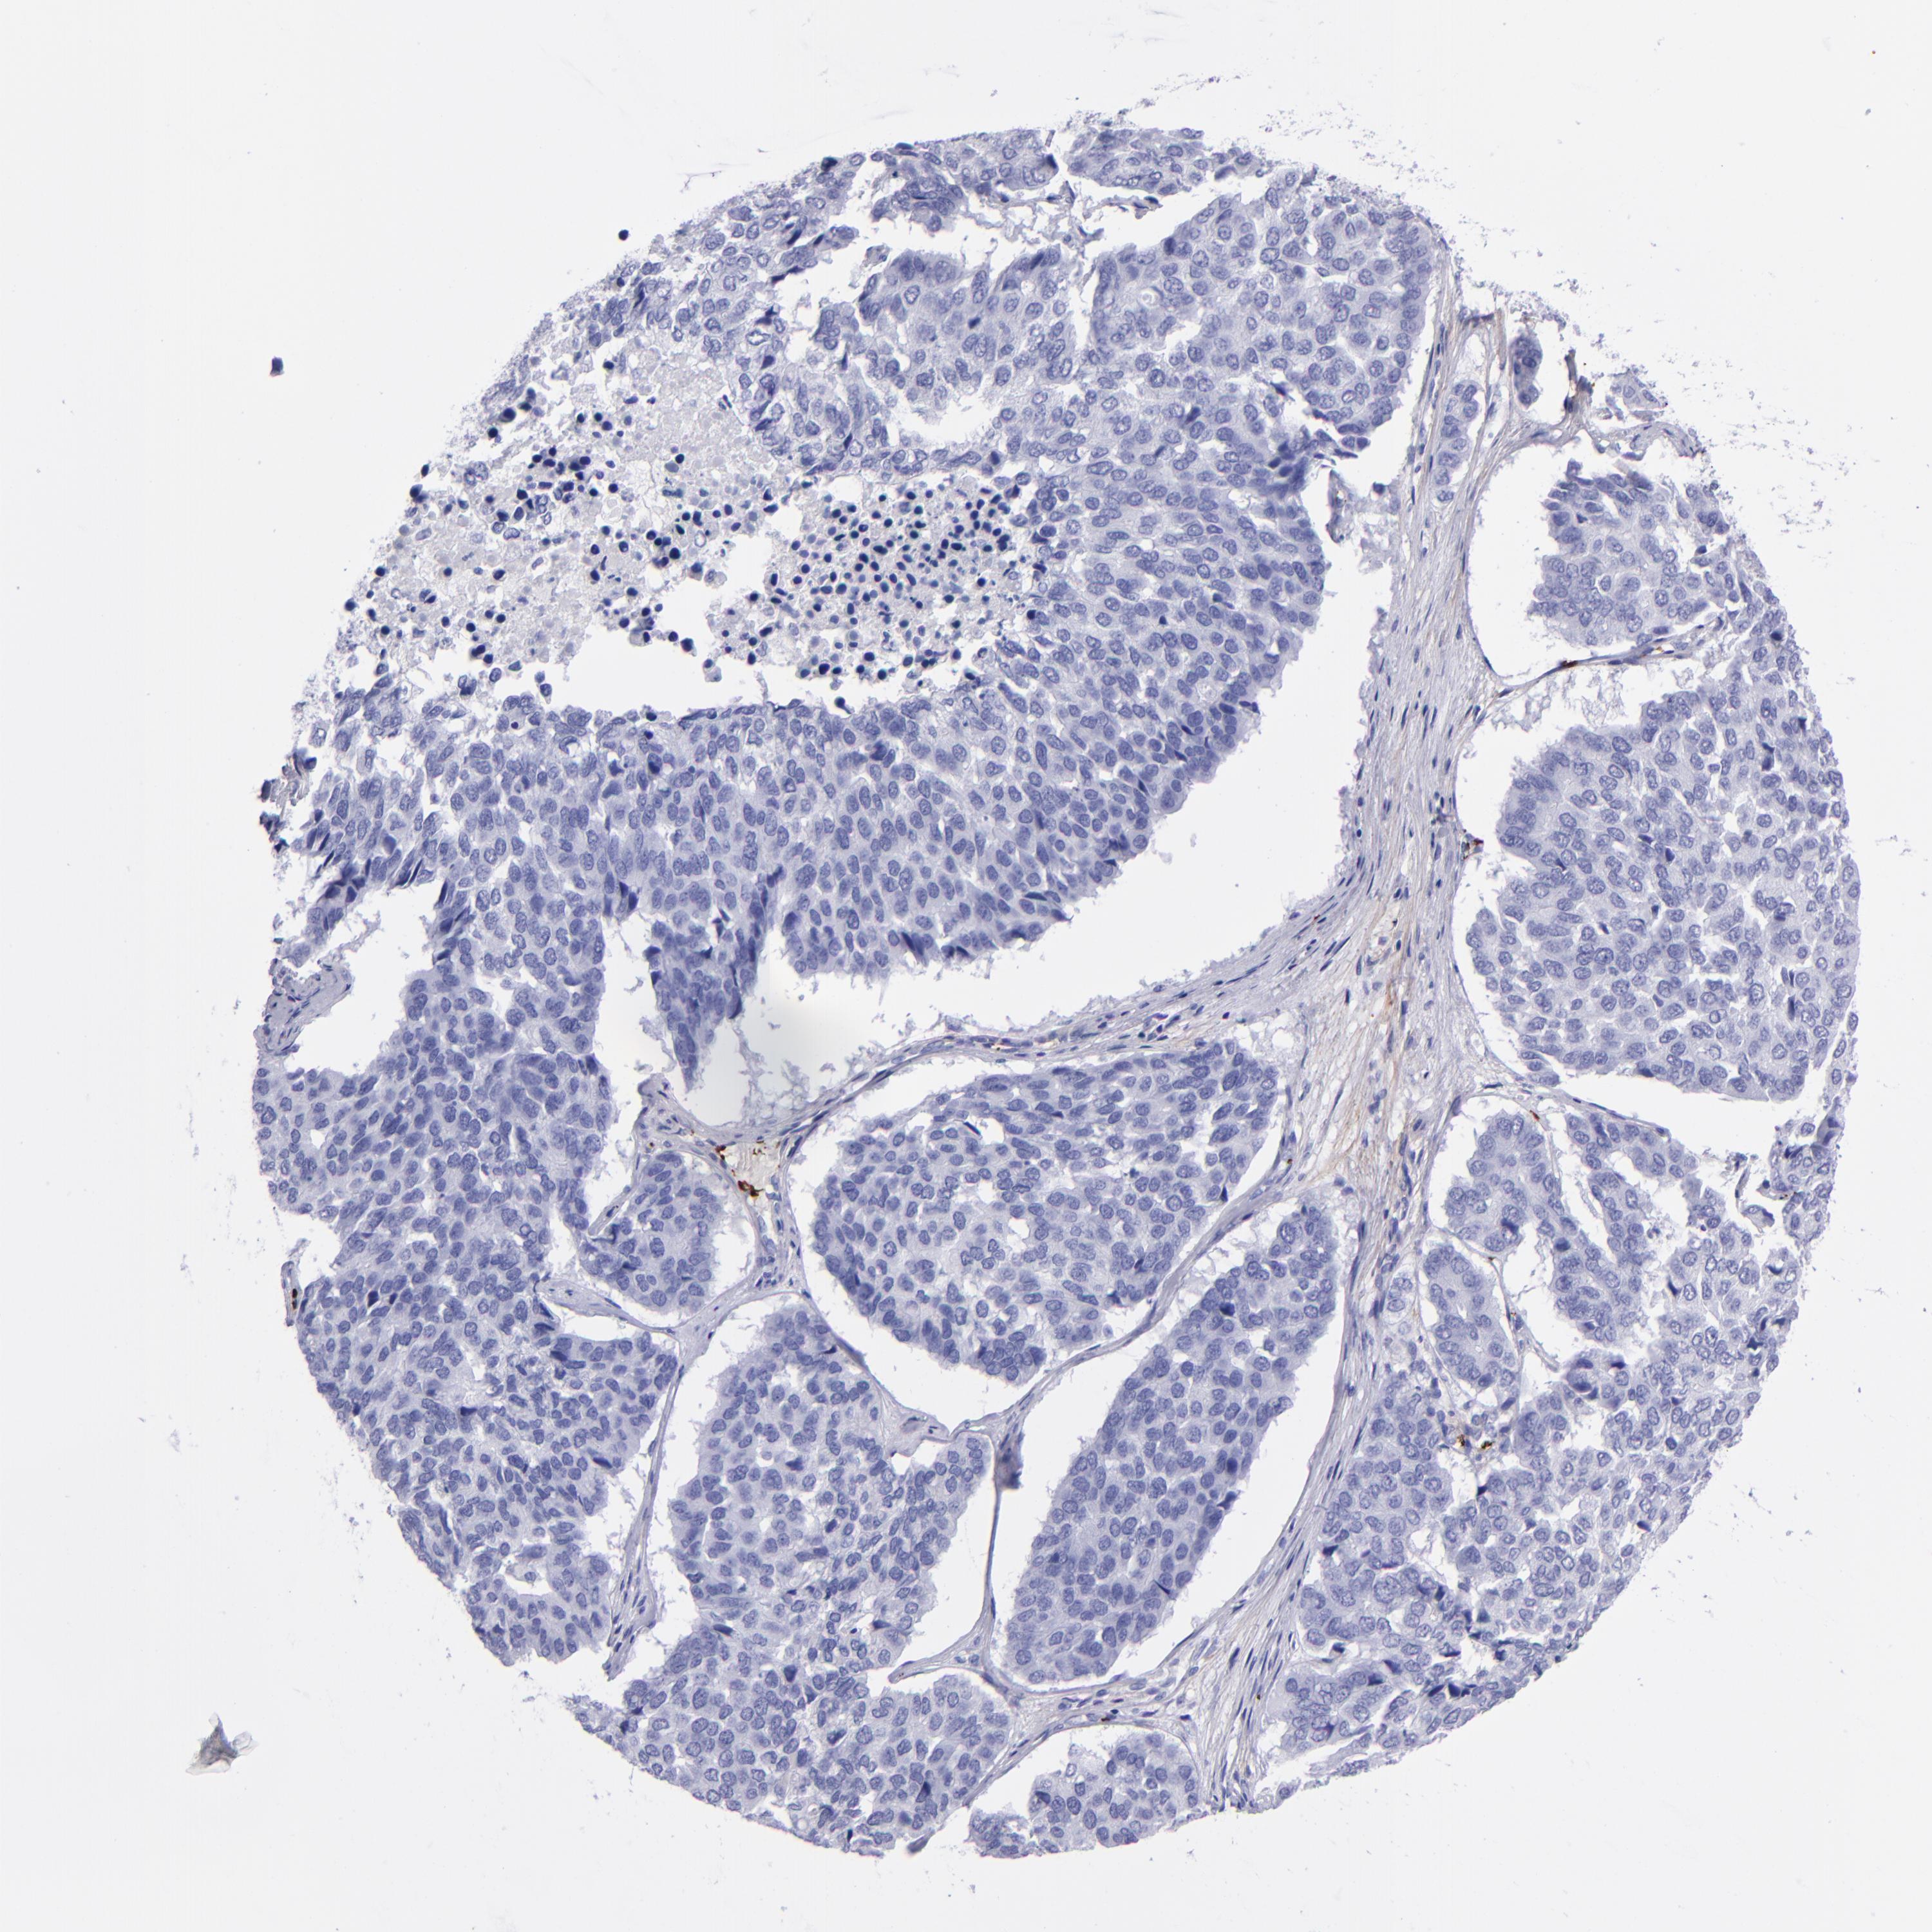

PANCREATIC CANCER - Protein expressioni

A mouse-over function shows sample information and annotation data. Click on an image to view it in a full screen mode. Samples can be filtered based on level of antibody staining by selecting one or several of the following categories: high, medium, low and not detected. The assay and annotation is described here.

Note that samples used for immunohistochemistry by the Human Protein Atlas do not correspond to samples in the TCGA dataset.

Antibody stainingi

Antibody staining in the annotated cell types in the current human tissue is reported as not detected, low, medium, or high, based on conventional immunohistochemistry profiling in selected tissues. This score is based on the combination of the staining intensity and fraction of stained cells.

Each image is clickable and will lead to virtual microscopy that enables deeper exploration of all samples and also displays staining intensity scores, fraction scores and subcellular localization as well as patient and tissue information for each sample.

Antibody HPA021633

Antibody HPA023249

Antibody HPA026561

Antibody CAB002501

Staining

Not detected

Intensity

Negative

Quantity

None

Location

Adenocarcinoma, NOS

Adenocarcinoma, metastatic, NOS